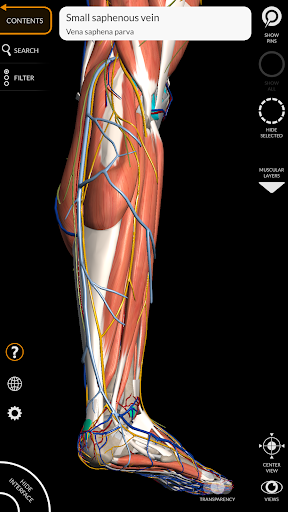

"Anatomy 3D Atlas" cho phép bạn nghiên cứu giải phẫu người theo cách dễ dàng và tương tác.

Thông qua giao diện đơn giản và trực quan, bạn có thể quan sát mọi cấu trúc giải phẫu từ mọi góc độ.

Các mô hình giải phẫu 3D đặc biệt chi tiết và có kết cấu lên đến độ phân giải 4k.

MÔ HÌNH GIẢI PHẪU 3D

• Hệ thống cơ xương

• Hệ thống tim mạch